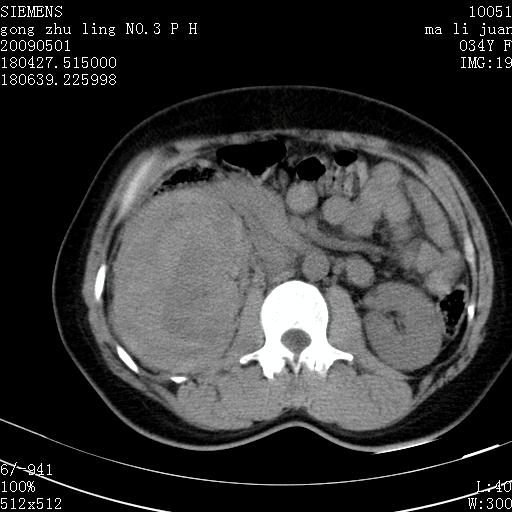

标题: CT19733:右肾碎裂

青年女性,骑摩托车摔伤。

右肾碎裂伤,包膜下血肿。

术中仅见右肾碎裂,肾蒂血管未见断裂。

支持 右肾破裂伴肾包膜下及肾周血肿。

右肾破裂并右侧腹膜后间隙出血。